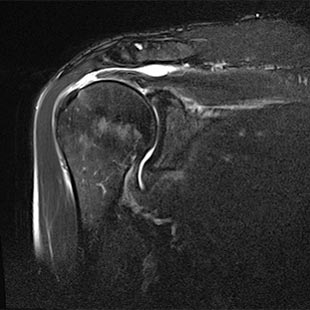

Abnutzungsbedingte Veränderungen im Alter und Stürze auf die Schulter oder auf die Seite können zu einem Riss der Rotatorenmanschette (= Muskel-Sehnen-Kappe der Schulter) im Schultergelenk führen. In den meisten Fällen ist die Supraspinatussehne betroffen.

Abriss der Sehne